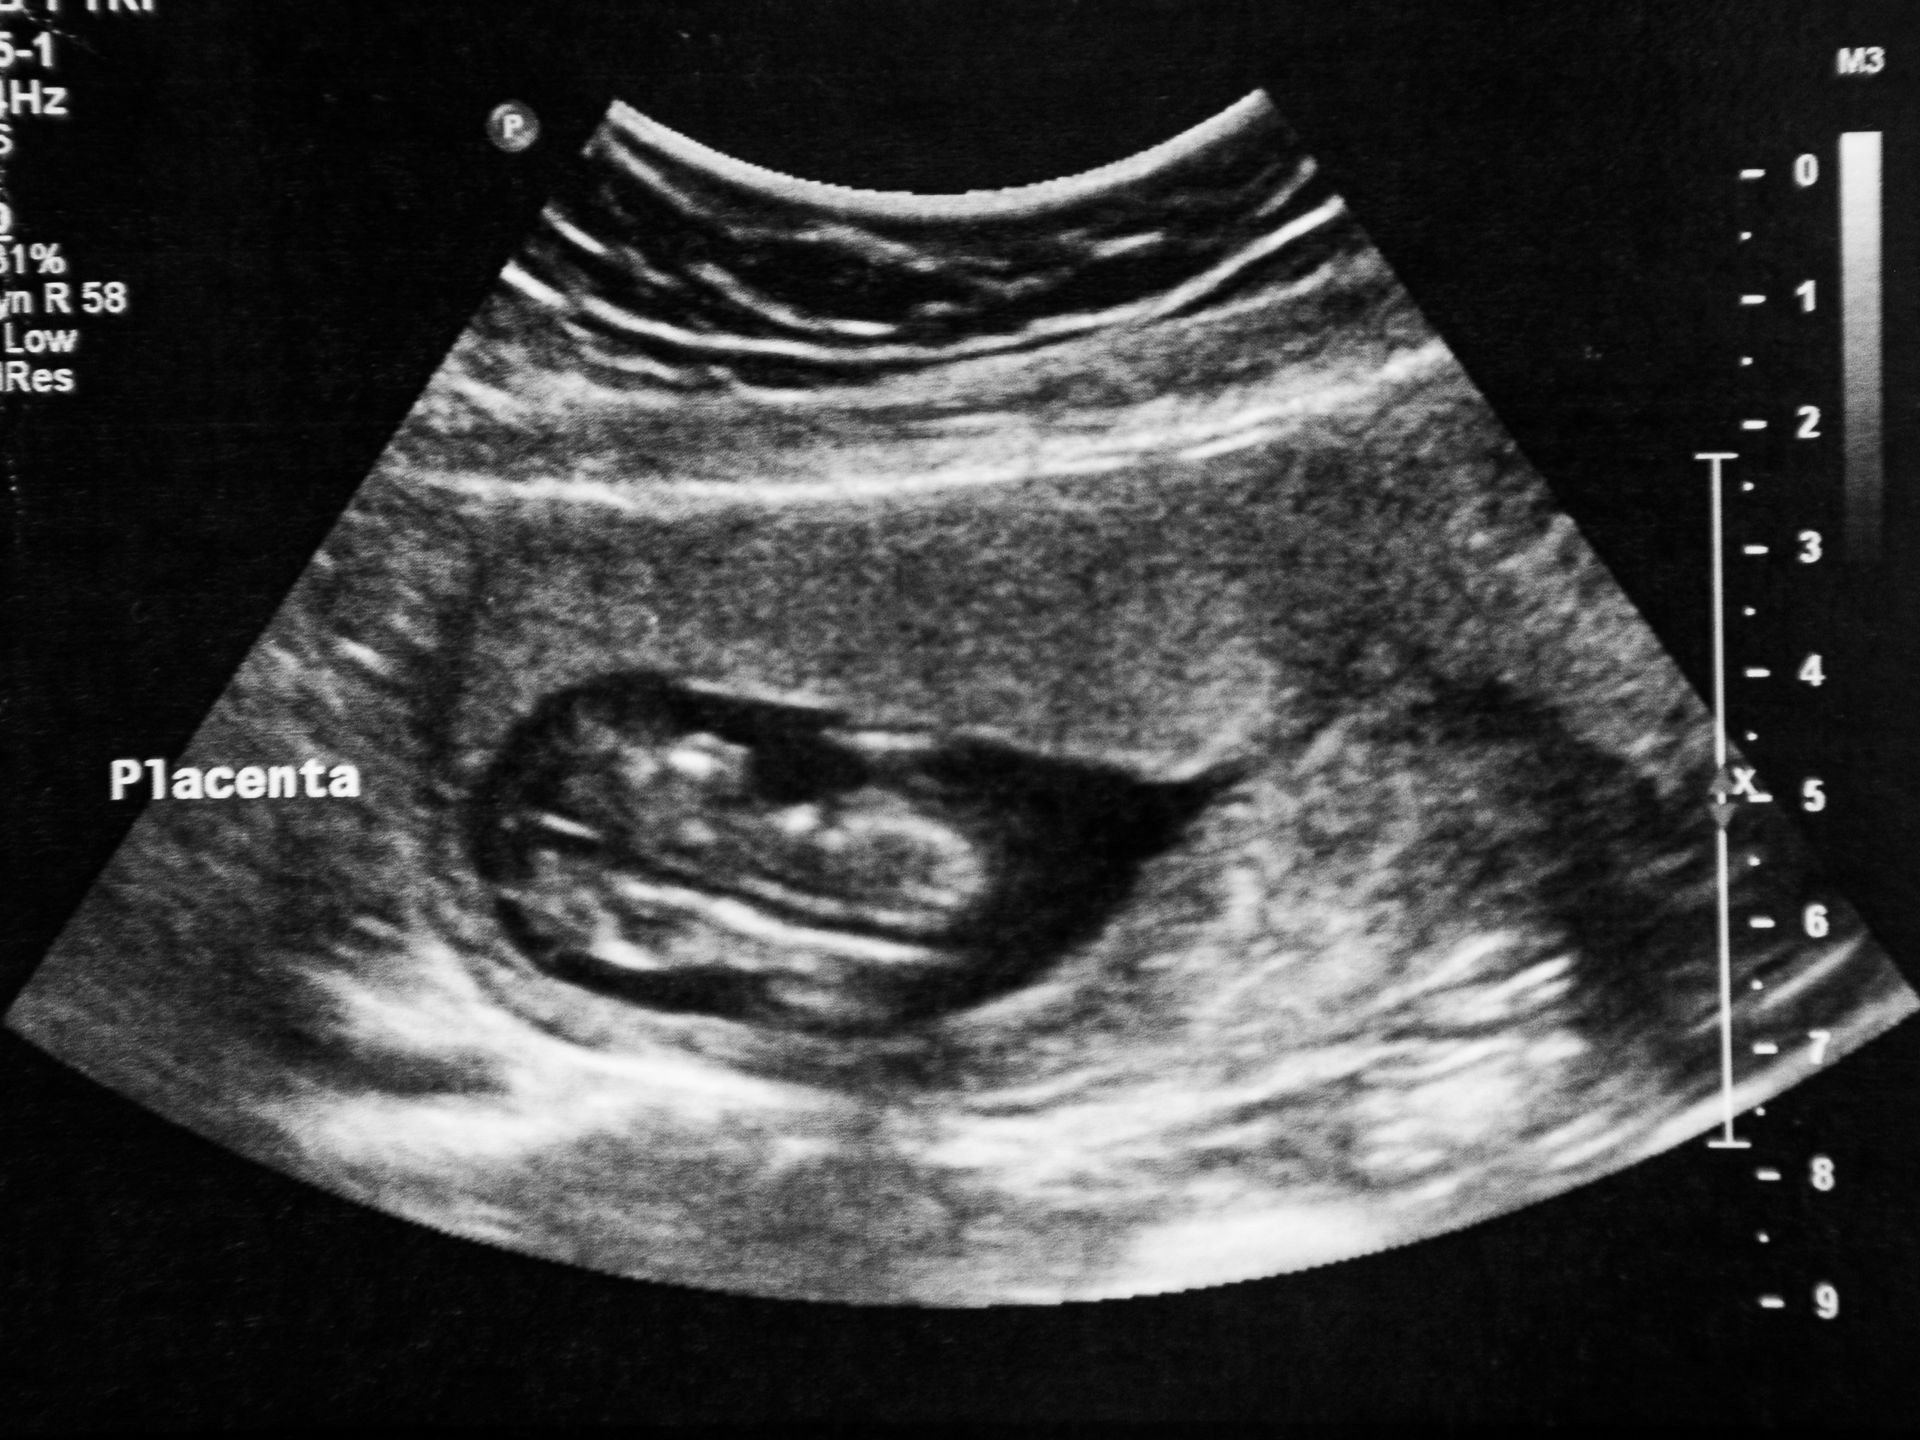

No Brasil, abortos espontâneos são comuns. Cerca de 23 milhões de gestações em todo o mundo terminam em aborto espontâneo a cada ano – isso é 15% do total ou 44 a cada minuto, de acordo com novas estimativas publicadas na revista médica The Lancet em 2022.

Confesso que a perda da Luna, minha filha, foi o princípio de todo esse projeto, a necessidade de validar a sua existência, de me validar como mãe e como mulher que deseja ser mãe, mas o tempo me mostrou que esse projeto vai muito mais além.